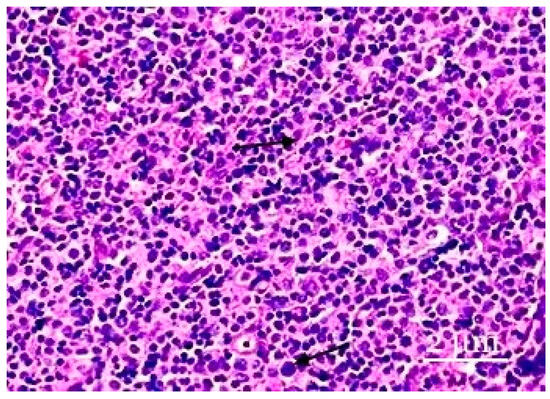

3. Results